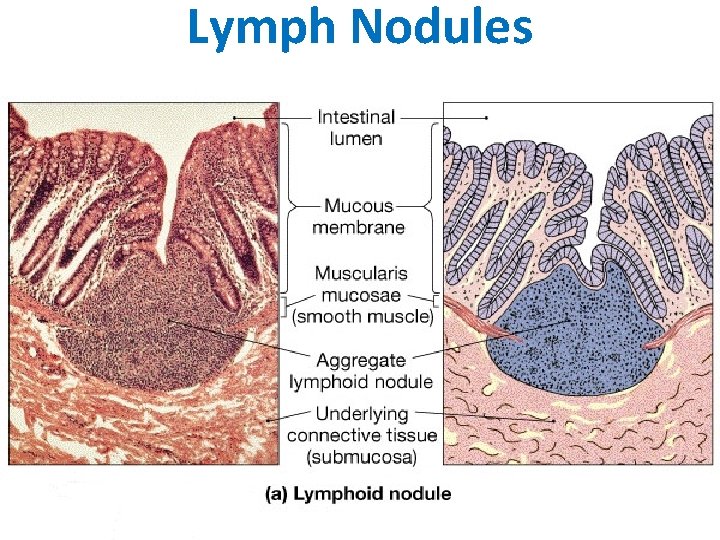

Lymphoid Nodules (Follicles): These occur in all lymphatic aggregates except the thymus. Active (lymphocyte-producing) nodules each have a darkstaining periphery, or mantle zone, that contains tightly packed small lymphocytes, and a light-staining core, or germinal center, that contains numerous immunoblasts (lymphoblasts), ie, lymphocytes stimulated by antigens to enlarge and proliferate. The lighter staining reflects the increased cytoplasmic volume and decreased nuclear heterochromatin that accompany lymphocyte activation.

Lymph Nodules

Lymphatic Nodule n n “Non-capsulated” Single or aggregated Independent OR parts of lymphoid organs Outer dark zone n n (Corona or cap) Germinal centre

Peyer’s Patches Smaller aggregates present under many mucous membranes : “Mucosa Associated Lymphoid Tissue” or MALT